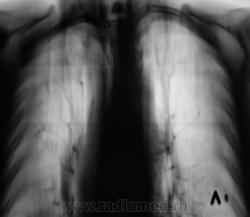

Архива нет. Эта флюорограмма была "первой". Ранее пациент проживал в другом районе.

При расшифровке флюорограмм, пациент "взят на контроль". Произведено стандартное дообследование.

Прямая дорога к фтизиатру. Неясно, что творится в средней доле, создается впечатление инфильтрации и наличия полости. Желательны ТГ ср. доли или хотя-бы прицельный снимок. Да и на правой верхушке поставить однозначно "остатачные явления" я бы не рискнул.

Да складывается впечатление о течении спецпроцесса. А в средней доли или инфильтрация или грудная мышца с соском. Но каков прицел!!! Заметить такую тенюху на верхушке а потом еще и раскрутить! Кстати Валентин Львович, а как на счет рентген нагрузки, как Вы полагаете сколько можно сделать томограмм, а то меня зав. третирует, что я выполняю по 5-6 томограм, причем они меньше Ваших максимум 24х30.

А справа на верхушке то не туберкулома?

да, туберкулома